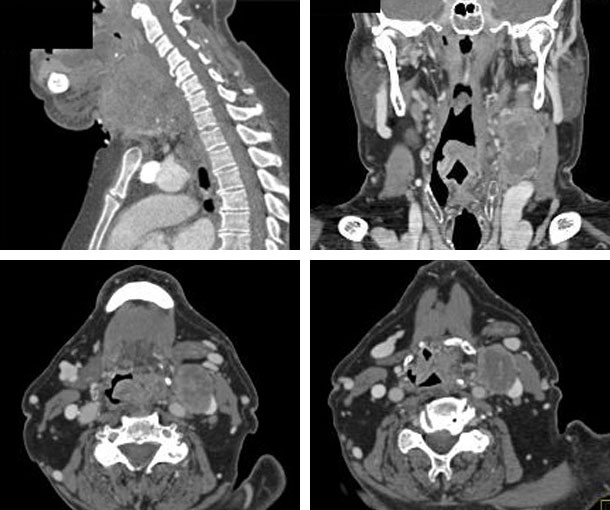

Laryngeal Cancer CT Findings

- Asymmetrical soft tissue thickening

- Abnormal enhancement

- Bulky mass

- Exophytic, infiltrative mass

- Obliteration of the normal fat planes

- Most originate in the laryngeal lining